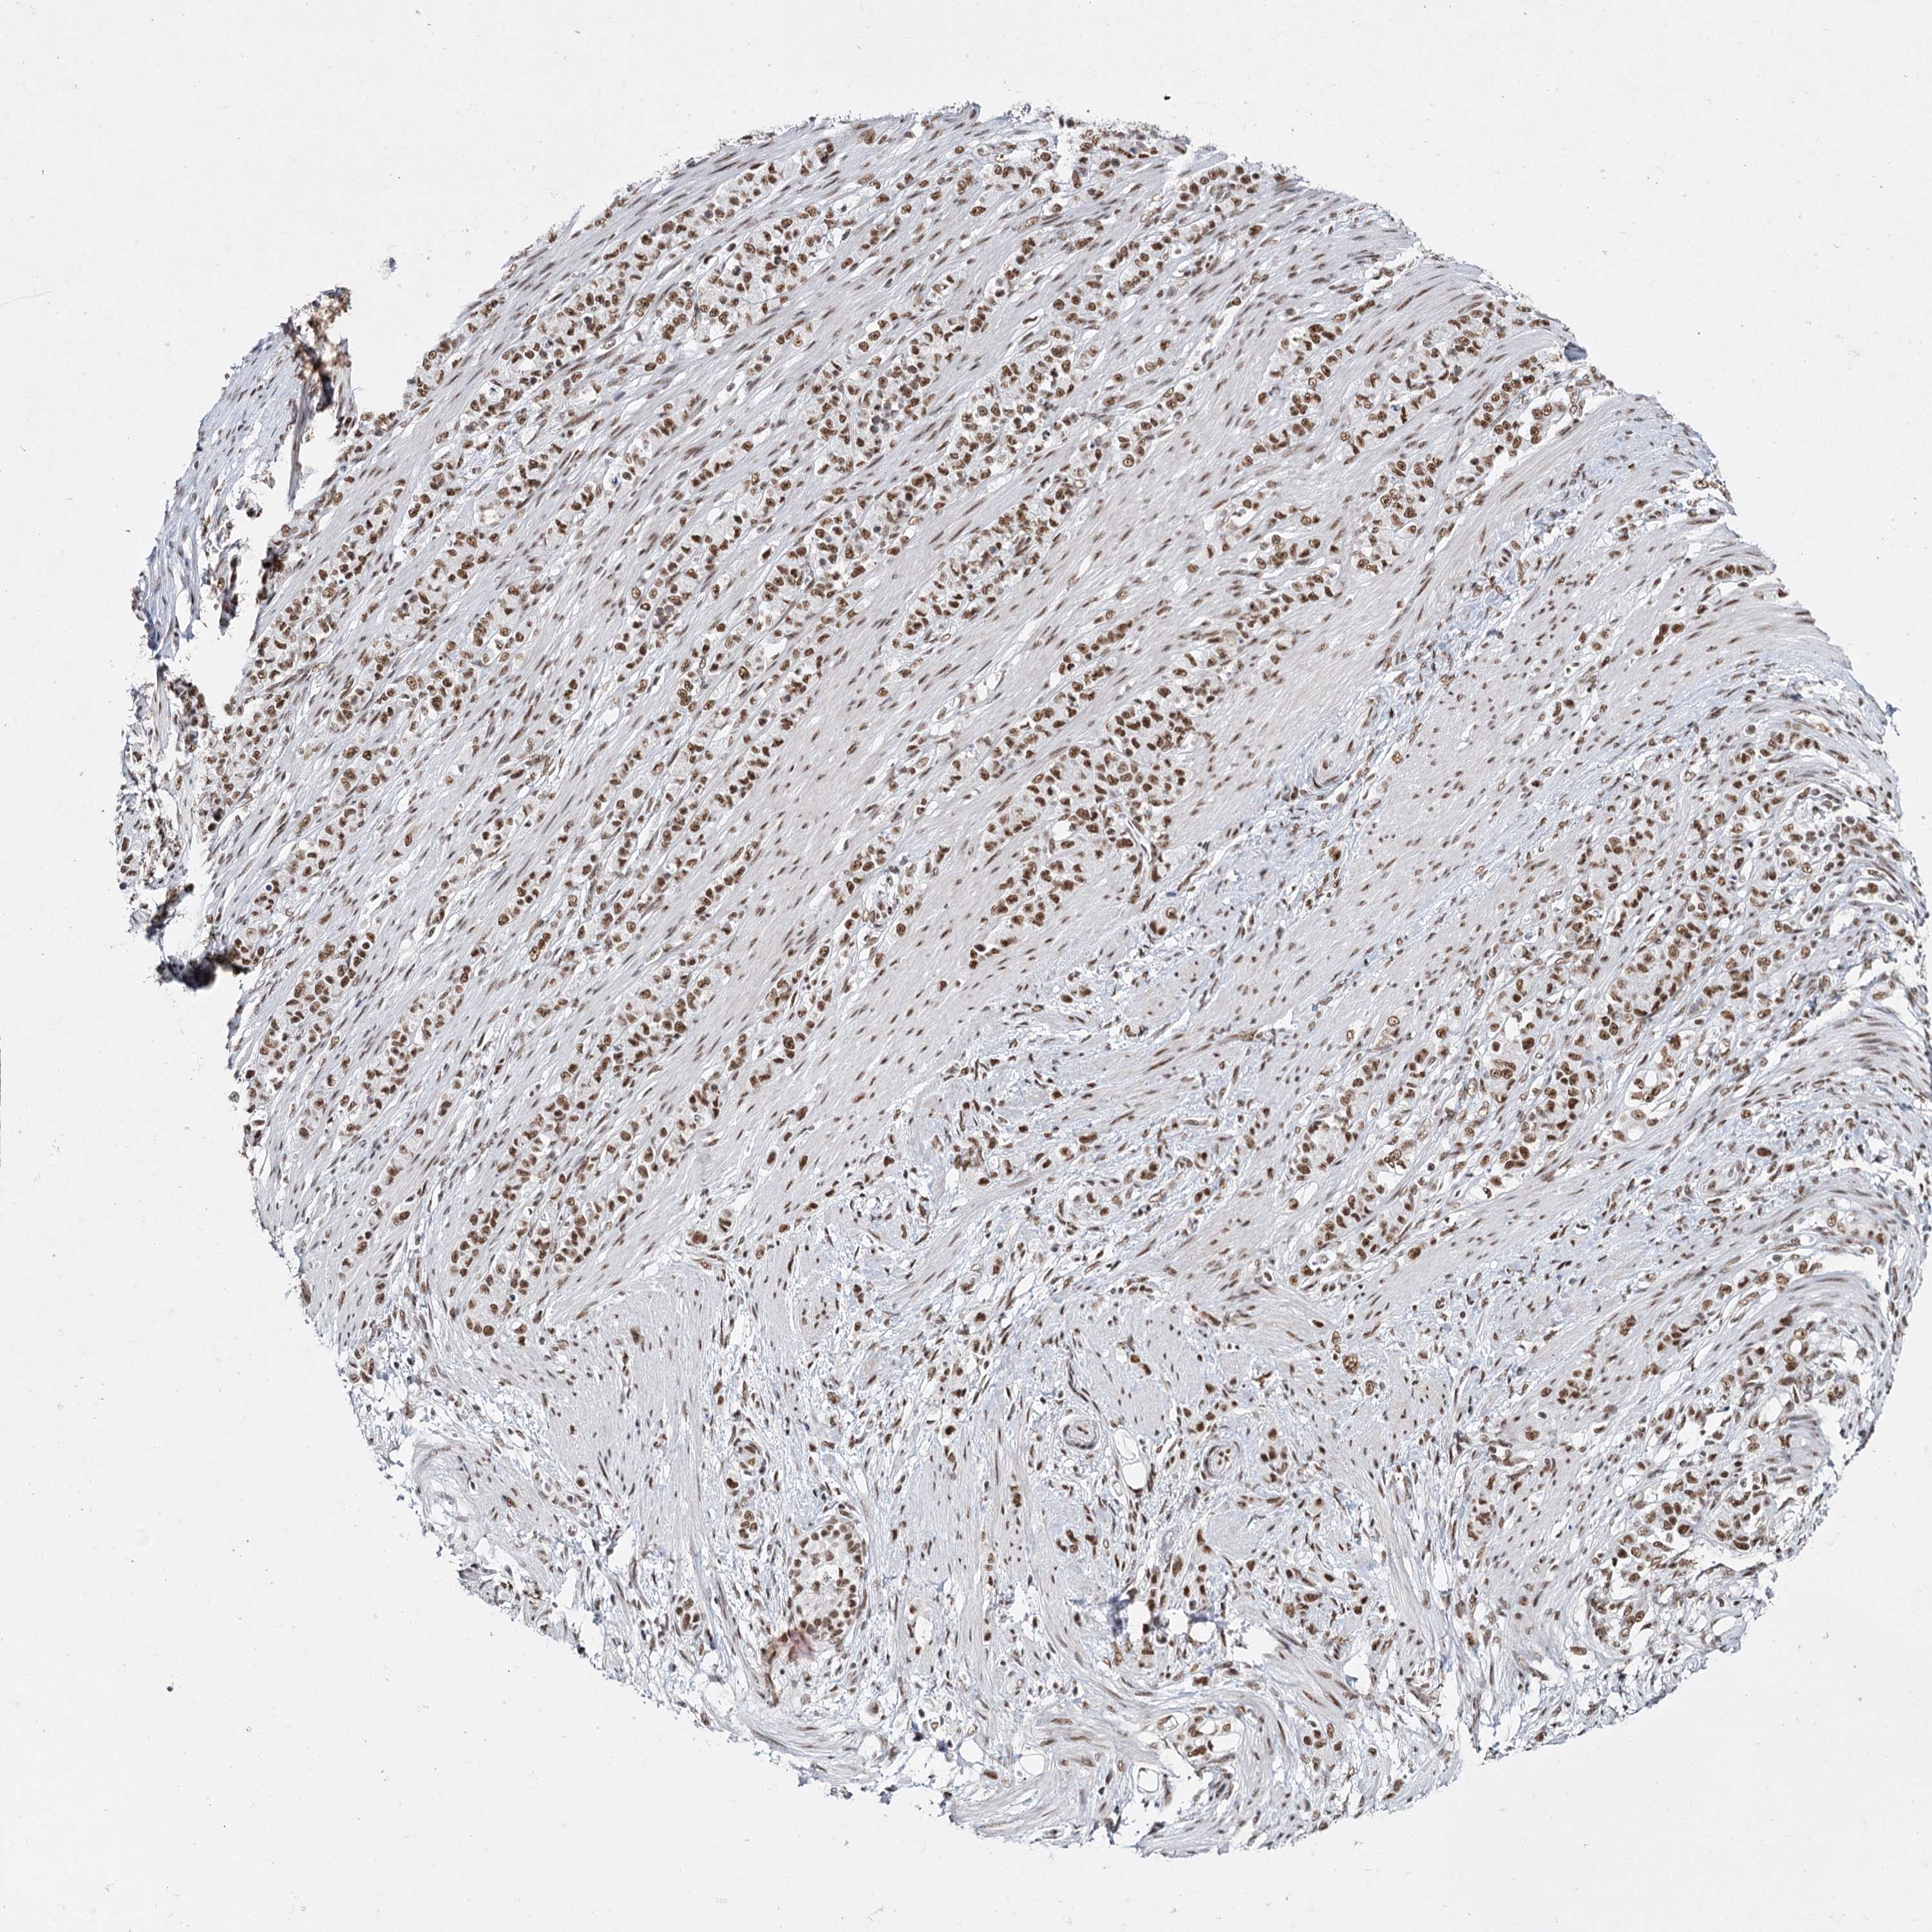

STOMACH CANCER - Protein expressioni

A mouse-over function shows sample information and annotation data. Click on an image to view it in a full screen mode. Samples can be filtered based on level of antibody staining by selecting one or several of the following categories: high, medium, low and not detected. The assay and annotation is described here.

Note that samples used for immunohistochemistry by the Human Protein Atlas do not correspond to samples in the TCGA dataset.

Antibody stainingi

Antibody staining in the annotated cell types in the current human tissue is reported as not detected, low, medium, or high, based on conventional immunohistochemistry profiling in selected tissues. This score is based on the combination of the staining intensity and fraction of stained cells.

Each image is clickable and will lead to virtual microscopy that enables deeper exploration of all samples and also displays staining intensity scores, fraction scores and subcellular localization as well as patient and tissue information for each sample.

Antibody HPA035601

Antibody HPA035602

Staining

High

Medium

Low

Not detected

Intensity

Strong

Moderate

Weak

Negative

Quantity

>75%

75%-25%

<25%

None

Location

Nuclear

Cytoplasmic/membranous

Cytoplasmic/membranous,nuclear

Adenocarcinoma, NOS